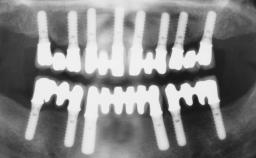

Immediate Loading of Six Implants in the Mandible and Six Implants in the Maxilla and Final Restoration with Full-Arch CAD/CAM Metal Framework FDPs Involving Digital Planning and Guided Surgery

Immediate loading of dental implants is increasingly popular with clinicians and patients. The idea of delivering a restoration directly after implant insertion,combined with a less invasive procedure (flapless protocol), has made treatment protocols involving dental implants more accessible to dentists and patients. However,immediate-loading concepts require sophisticated and exact planning. To facilitate this, conventional panoramic tomographs and periapical radiographs are often taken with the patient wearing a radiographic template simulating the preoperative prosthetic design. However, these radiographs do not provide all the necessary information. In addition, some protocols call for conventional surgical templates fabricated on the diagnostic cast. These will inform the bone drilling points and drill angles, but do not reference the underlying anatomical structures or provide exact 3-D guidance.

# of Implants 12

Type of Implants One-Piece

Guided Surgery Yes